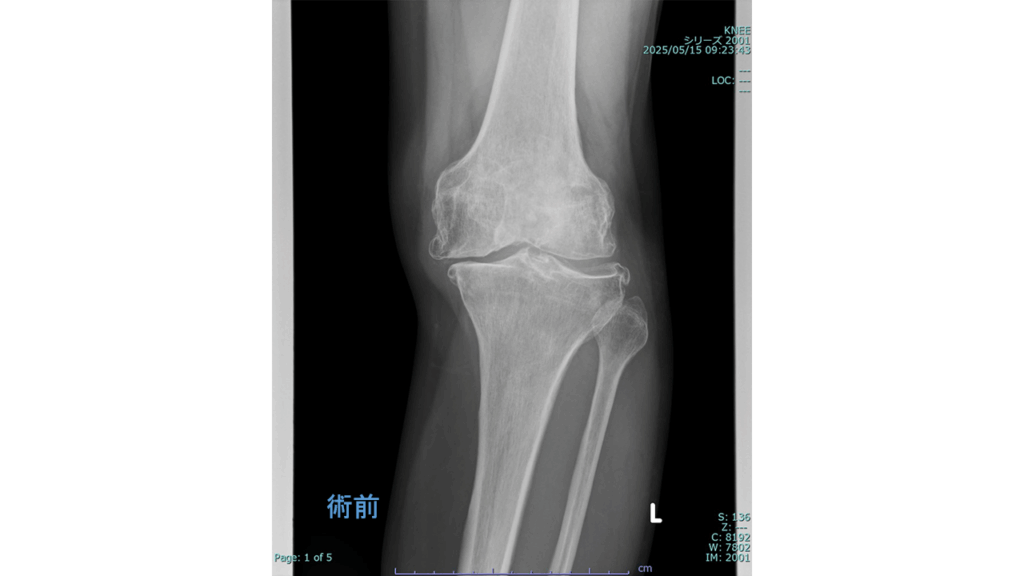

変形性膝関節症に対する手術

◆人工膝関節全置換術

(Total Knee Arthroplasty:TKA)

入院期間 3~4週間

外来リハビリ 2~3か月

術前